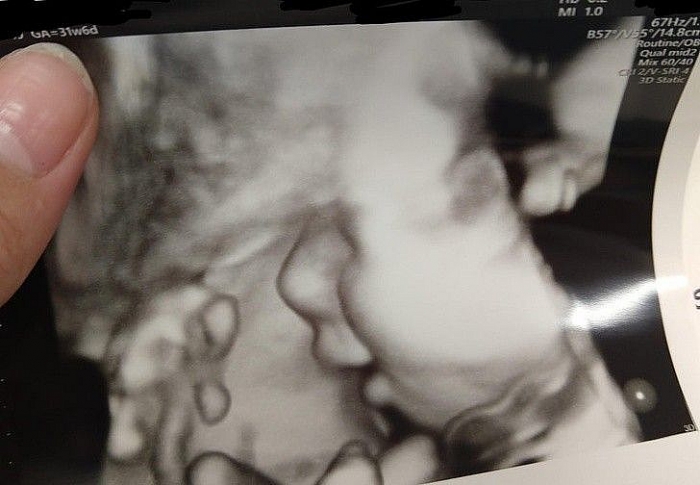

| "Sau nhiều nỗ lực thụ thai không thành công, khi phát hiện ra mình có thai lần nữa, tôi vô cùng lo lắng. Trong một lần đi siêu âm, con trai tôi mỉm cười! Tôi rất yêu con và tôi đã khóc khi nhìn thấy điều này". (Nguồn: Brightside) |